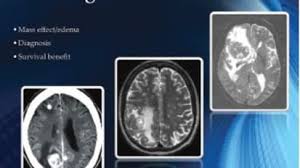

This white paper explores the treatment of brain and spinal cord cancer which is dependent on the on the tumor’s size, location, and type, as well as the patient’s age and general health.

Stereotactic Radiosurgery (SRS) at John Muir Health TRUE Radiosurgery >

A collaboration of the JMH Neuroscience Institute and JMH Cancer Institute Providing “best in class” treatment and care.